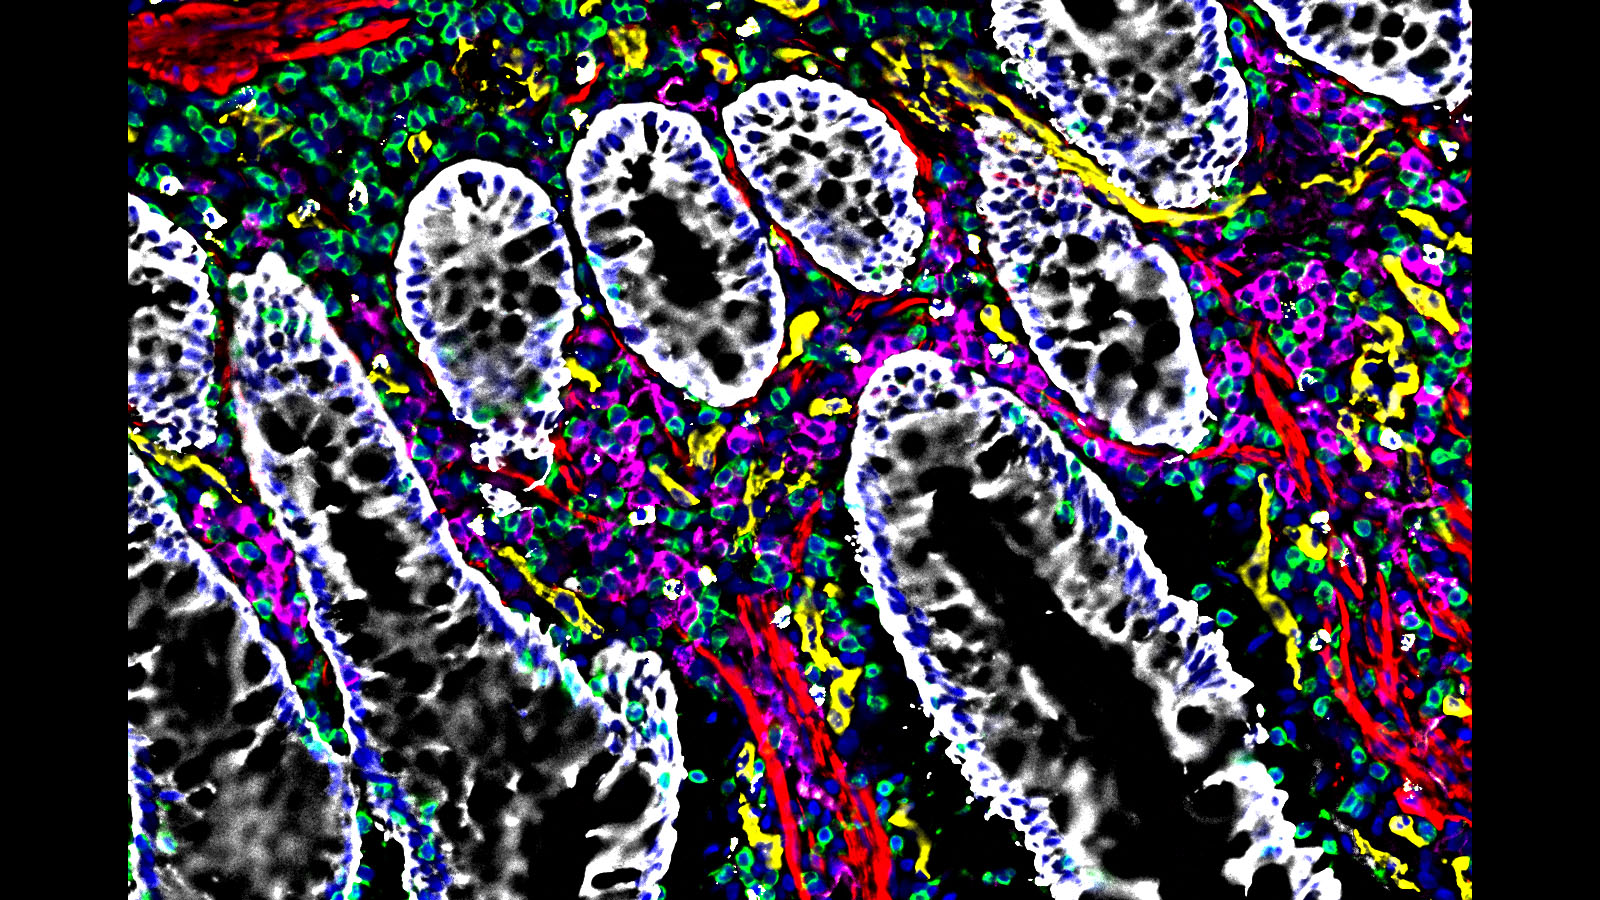

Some of the most amazing things to come out of the HuBMAP Consortium are the images of healthy human tissues generated by our researchers.

Here, we collected them in one place to celebrate the work of these talented individuals.

#CODEX image of the intestine courtesy of @stanford researcher Dr. John Hickey